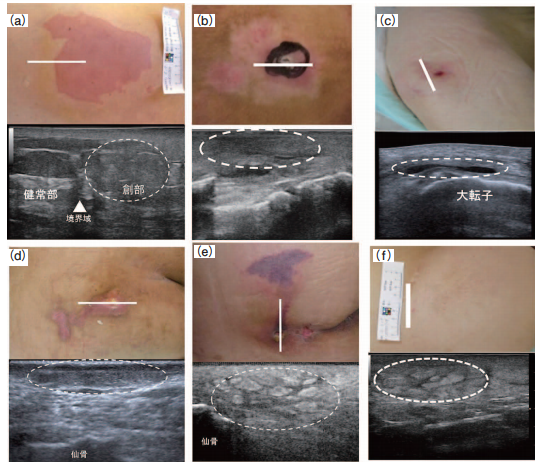

褥瘡エコーの個人的マニュアル - 南砺の病院家庭医が勉強記録を始めました。An archive of medical articlessummarized by a family physician from Nanto Municipal Hospital。

はじめての褥瘡エコー 前編 かんかん! -看護師のためのwebマガジン by 医学書院。

褥瘡エコーの個人的マニュアル - 南砺の病院家庭医が勉強記録を始めました。An archive of medical articlessummarized by a family physician from Nanto Municipal Hospital。

はじめての褥瘡エコー 前編 かんかん! -看護師のためのwebマガジン by 医学書院。

はじめての褥瘡エコー 前編 かんかん! -看護師のためのwebマガジン by 医学書院。

はじめての褥瘡エコー 前編 かんかん! -看護師のためのwebマガジン by 医学書院。